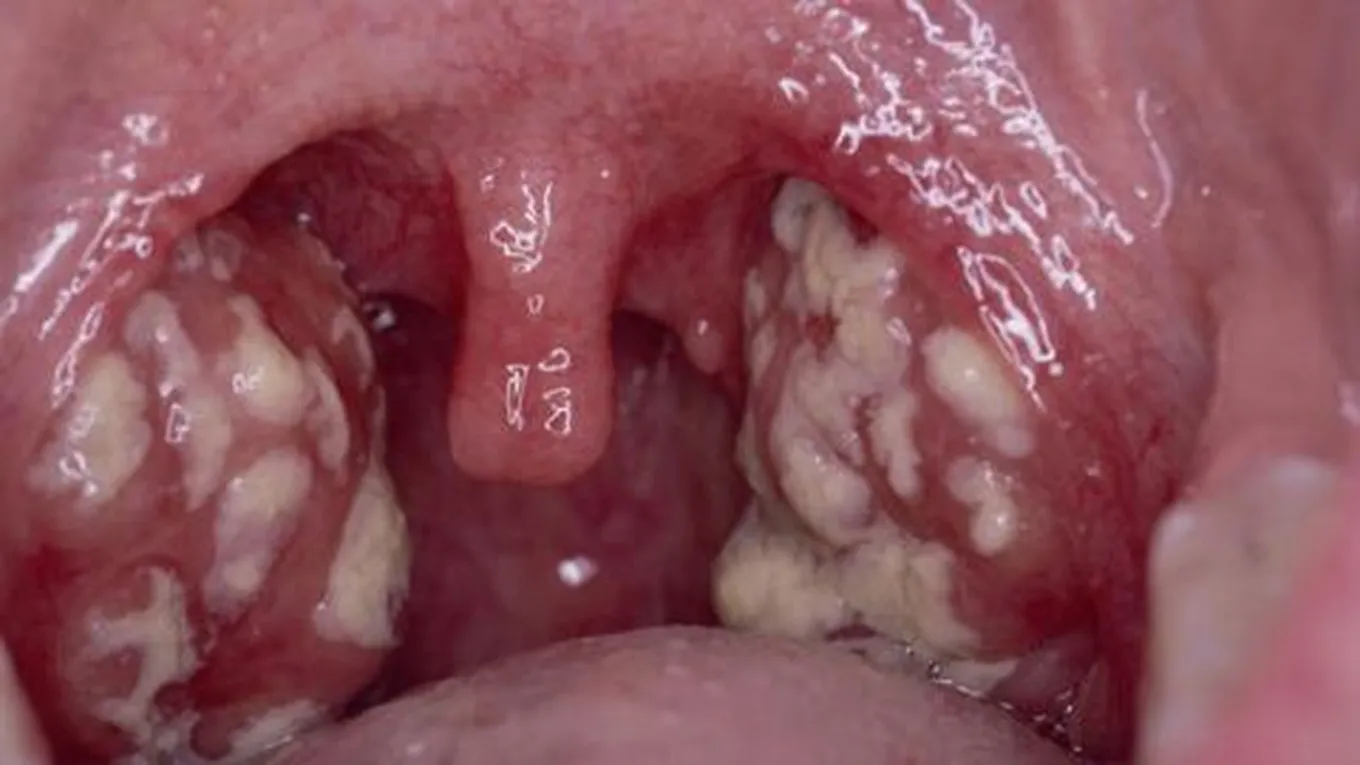

تُعرف اللوزتين بأنّهما زوج من الأنسجة الرخوة الموجودة في مؤخرة الحلق أو ما يُسمى بالبلعوم (بالإنجليزية: Pharynx)، وتتكون اللوزتين من أنسجة مشابهة للغدد الليمفاوية، وتكون مغطاة بغشاء مخاطي وردي، وقد تتفاوت في الحجم من شخص إلى آخر، وتُعدّ الوزتين جزءاً مهماً من الجهاز الليمفاوي الذي يساعد على محاربة العدوى؛ إذ تتضخم اللوزتين استجابة للعدوى، وعلى الرغم من ذلك فقد وُجد أنّ إزالة اللوزتين لا تزيد من فرصة الإصابة بالعدوى.[1]

هناك مجموعة من الأسباب التي تؤدي إلى وجود بقع بيضاء على اللوز أو ما يُعرف بصديد اللوز، ويعتمد علاج صديد اللوز على المسبب الذي أدَّى إلى ظهوره،[2] وفيما يلي بيان لأهم أسباب صديد اللوز وعلاج كل منها:

- حصى اللوزتين: تتشكل حصى اللوز نتيجة تجمع خلايا الجلد الميتة، وخلايا الدم البيضاء، والبكتيريا، في الجيوب الموجودة في اللوزتين، إذ تصبح هذه المكونات مشبعة باللعاب، ومتكلّسة لتُشكّل كرة تشبه الحجر، ومن الجدير بالذكر أنّ علاج حصى اللوزتين ليس ضرورياً في العديد من الأحيان، إلا إذا كان المصاب يشعر بالانزعاج الشديد منهم، لأنّ الجسم سيحاول التخلص من حصى اللوزتين من تلقاء نفسه، ولكن يمكن رش الماء المالح على اللوزتين لمحاولة تنظيف بعض الرواسب، وتجدر بنا الإشارة إلى أنّ النساء أكثر عرضة للإصابة بحصى اللوزتين من الرجال بنسبة 33%، والسبب غير معروف حتى الآن، كما بينت الدراسات أنّ العمر يلعب دوراً مهماً في زيادة خطر الإصابة بحصى اللوزتين، حيث إنّ الأطفال أقل عرضة للإصابة بحصى اللوزتين مقارنة بالمراهقين والبالغين.[4][2]

قد تظهر على المصاب بعض الأعراض تدل على احتمالية تشكل صديد اللوز، ومن هذه الاعراض ما يلي:[9]

- انتفاخ أو التهاب أجزاء من الفم والحلق وعادة ما يكون ذلك في جانب واحد.

يُعرف التهاب اللوز (بالإنجليزية: Tonsillitis) بأنّه عدوى تصيب اللوزتين، وغالباً ما يحدث نتيجة التعرض لعدوى فيروسية، كما يمكن أن ينجم التهاب اللوزتين عن التعرض لبعض أنواع البكتيريا،[10] ومن الجدير بالذكر أنّ المضاعفات التي يُمكن أن تنجم عن التهاب اللوزتين تُعتبر نادرة الحدوث، وتتضمن هذه المضاعفات ما يأتي:[11]